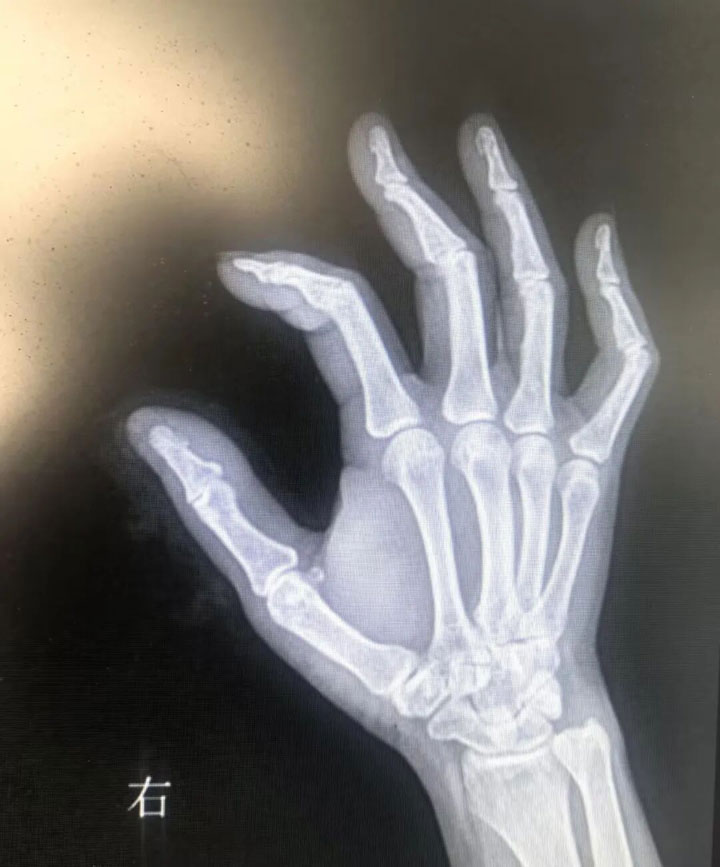

上周不小心手外伤,着急就在附近医院包扎,但是有个小铁屑在手指里无法取出,问了几个医生,两家医院都说不好取,甚至有医生说,“这么小,不取也不妨碍!”我们听后心里十分不舒服,后向火车站东方综合门诊求助。医护人员很热心的帮我们向陶勇医生咨询,随即联系我们前往东方总医院。

患者上周不慎手外伤,右手拇指残留异物,因异物太小无法取出,辗转几家医院无果,后求助东方集团综合门诊,联系了东方总院骨科陶勇主任。陶主任主动延迟下班,术中全程耐心细致,顺利为患者取出手中异物,没有因已经下班而有丝毫的推脱与敷衍。手术室护士全程陪伴安抚,让患者感动又佩服,一直称赞“为患者排忧解难,又医术精湛,东方总院是名符其实的三甲医院!好医院才能培养出这样好的医生护士!”